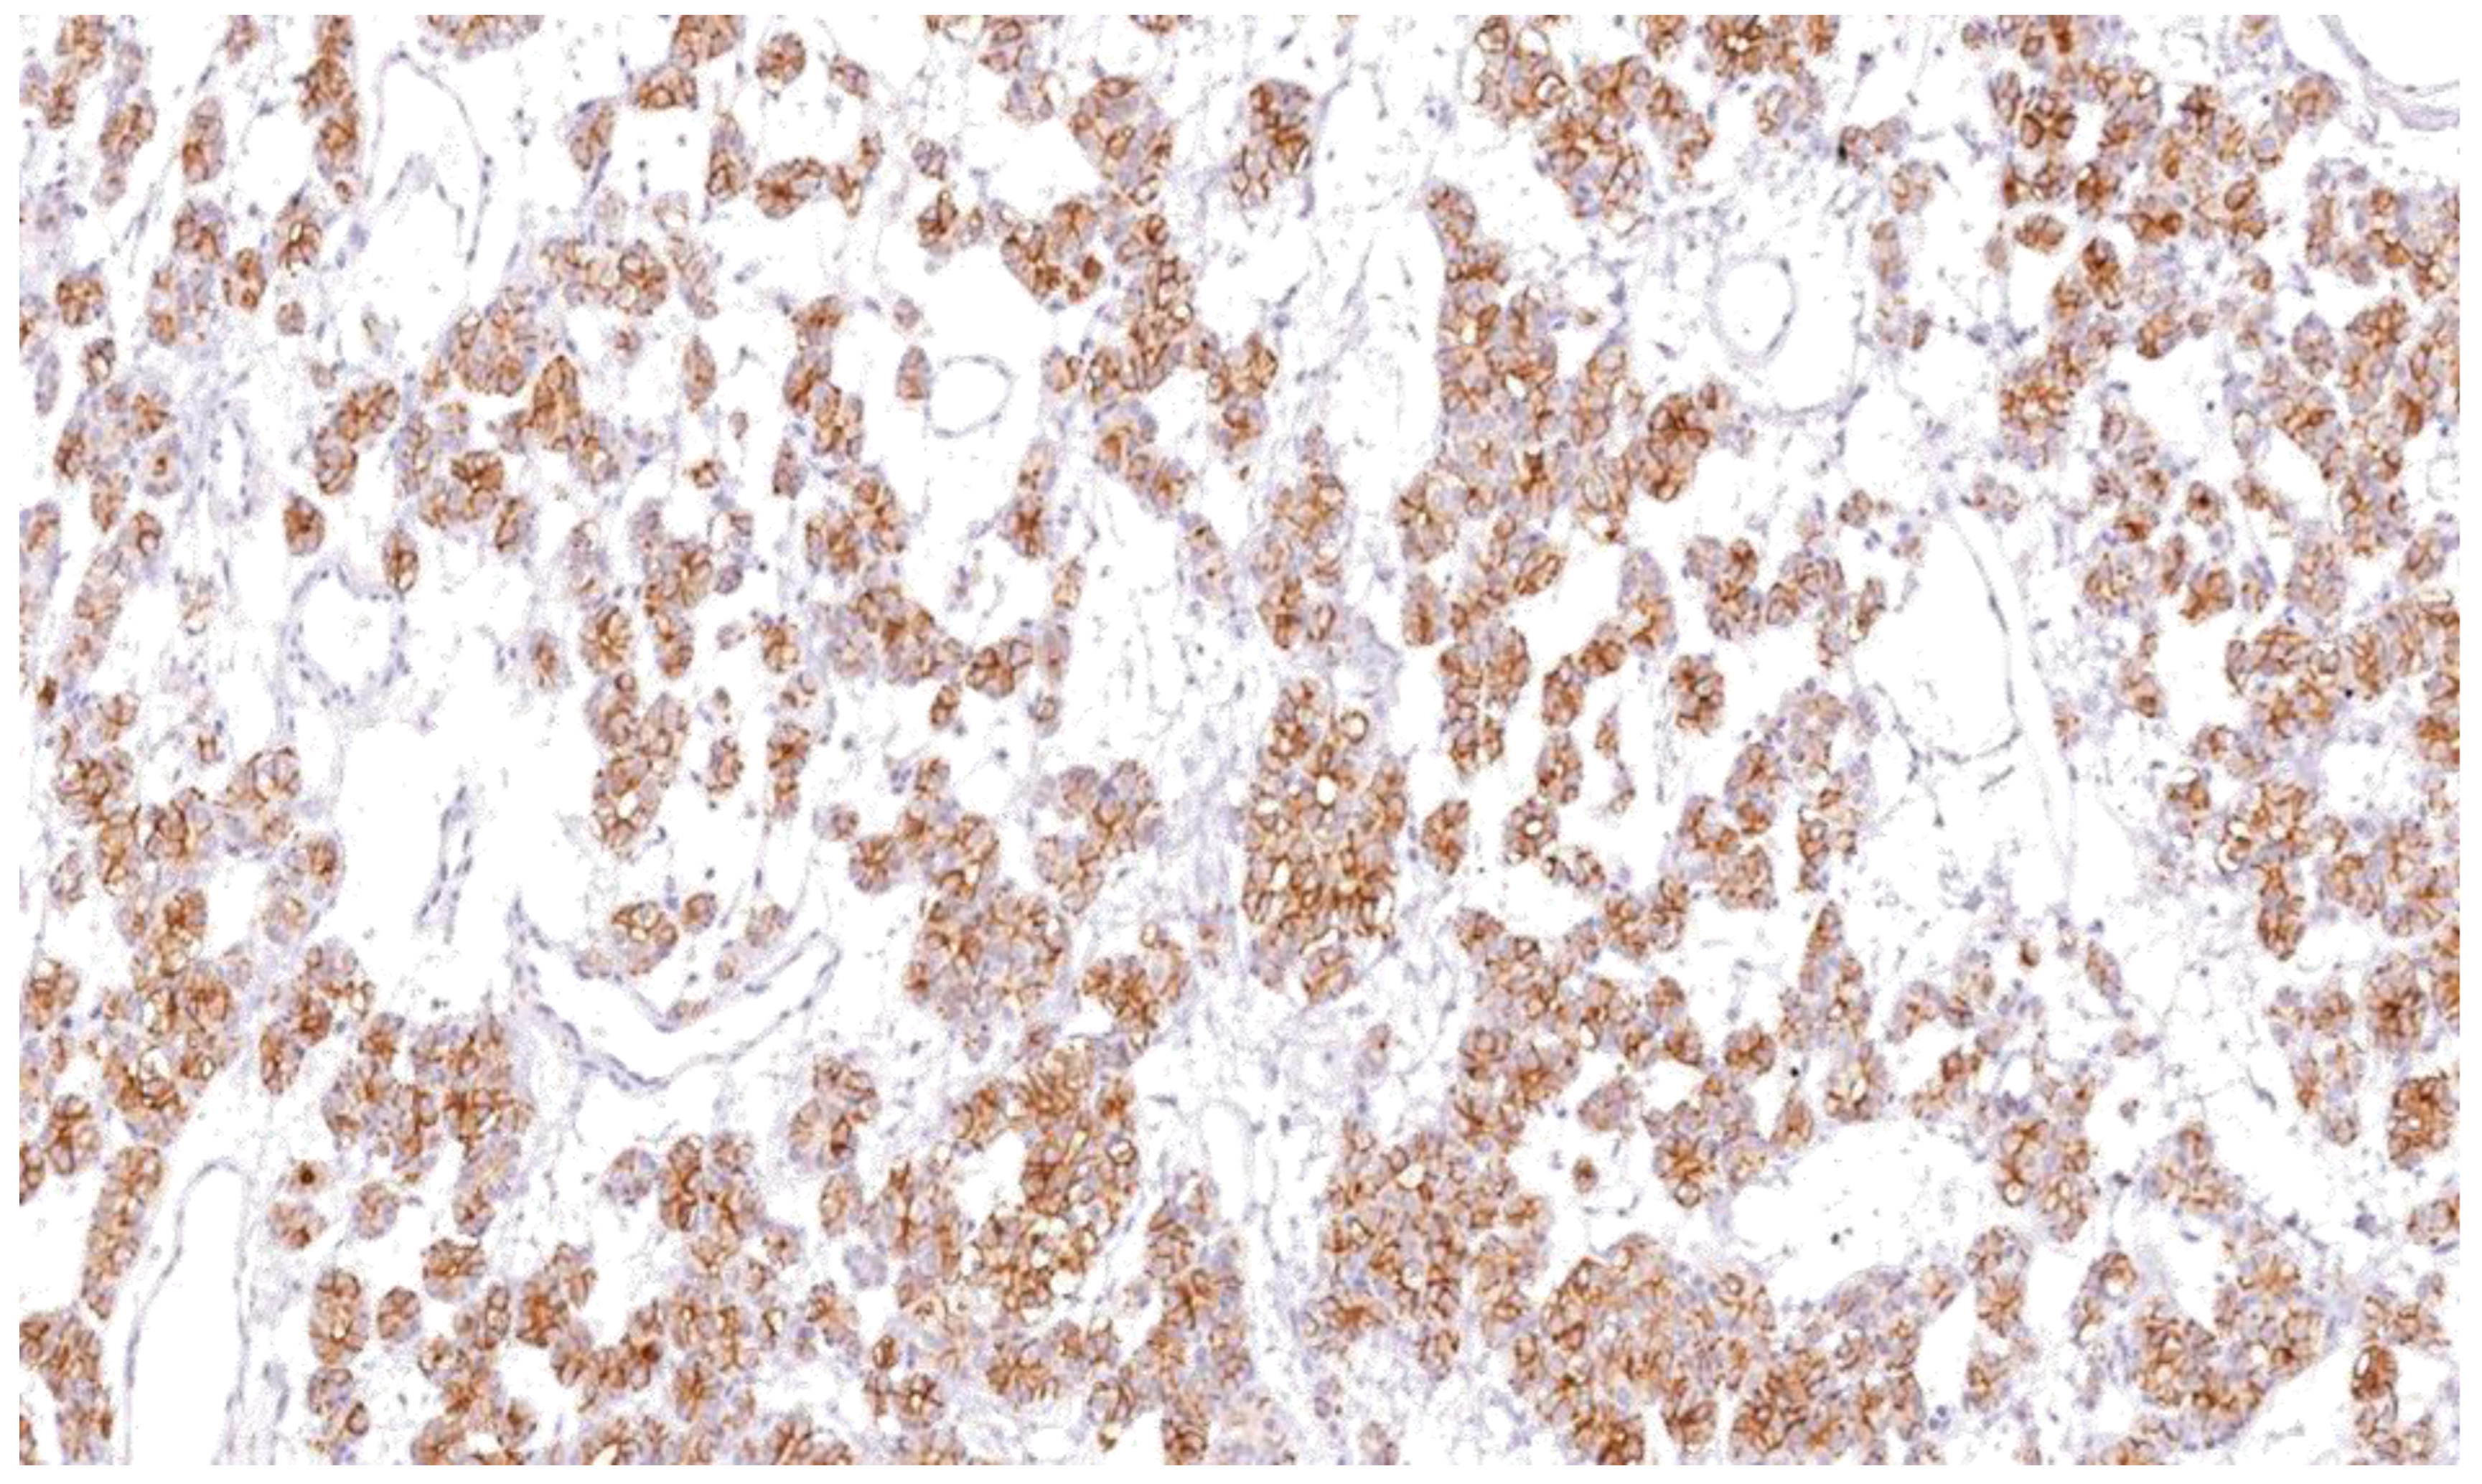

4.1. Immunohistochemical Results

| Thyroid Carcinoma | Papillary carcinoma | 80.49 | 0.012 | 68.28 | 0.002 |

| Follicular carcinoma | 30.80 | 42.34 | |||

| Medullary carcinoma | 5.07 | 26.66 | |||

| Anaplastic carcinoma | 7.29 | 23.24 | |||

| Benign Thyroid Lesions | Follicular adenoma | 3.42 | 0.821 | 20.91 | 0.220 |

| Lymphocytic thyroiditis | 5.01 | 22.39 | |||

| Multinodular goiter | 3.91 | 30.20 | |||

| Normal thyroid tissue | 4.03 | 20.94 | |||